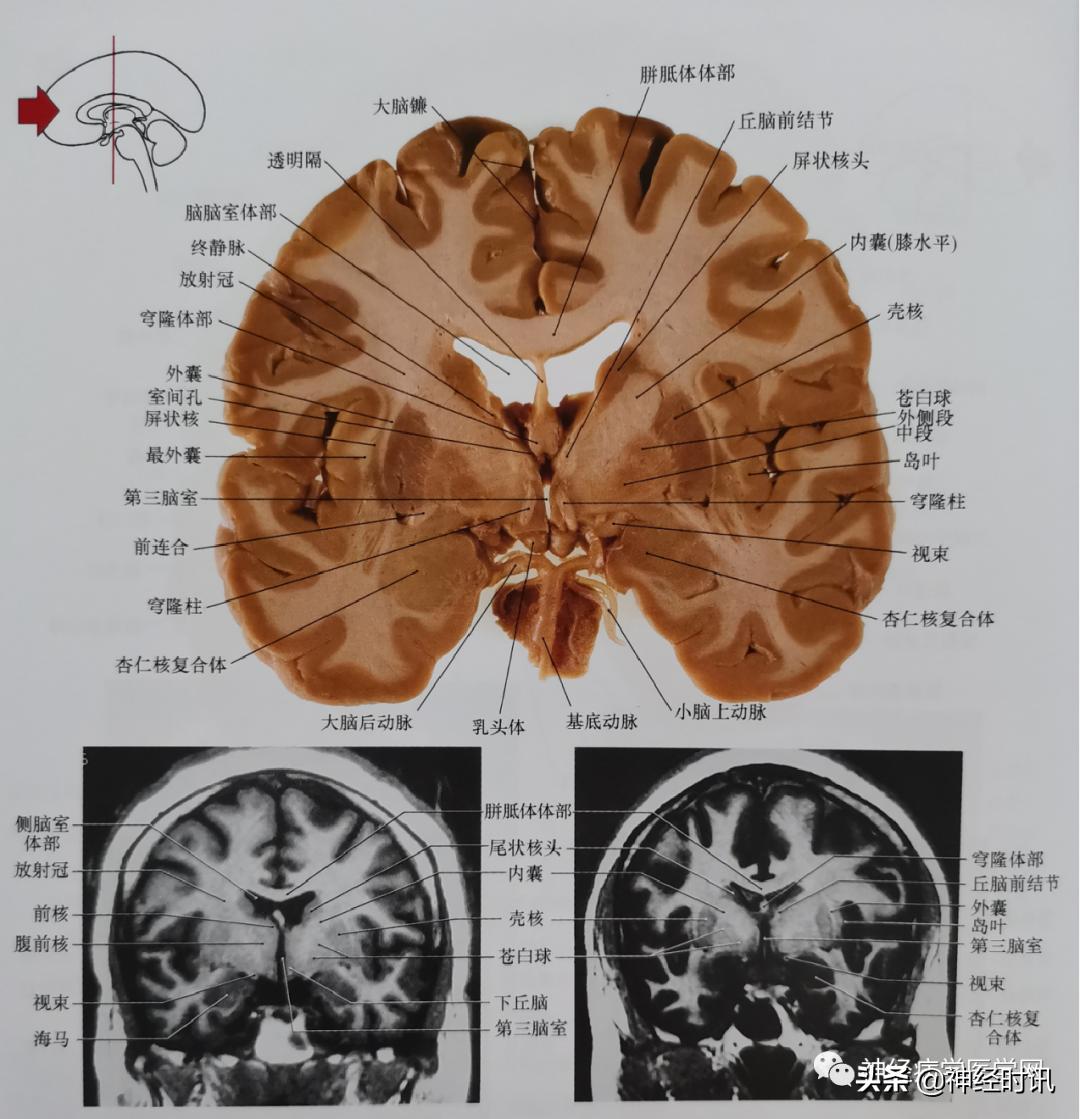

图2 通过前连合即内囊膝部与穹窿柱平面的冠状位嘴侧面影像。与图1相比,尾状核显示较小,苍白球比较明显,内侧邻近壳核。

图3 通过丘脑前结节及穹窿柱(前连合尾侧)平面的冠状位影像。此平面也通过内囊膝部。此平面亦包括苍白球的两部分;内侧(内段)部分及外侧(外段)部分。终静脉丘纹上静脉。

海马位于侧脑室颞角的腹内侧面,在磁共振影像中表现出的纹理代表其细胞体部与纤维相交错的层次关系(可参见图4)。另一方面,杏仁核位于颞角的嘴端,影像学中信号均匀一致(如图)。简单总结一下这些结构的关系,即海马为脑室内带有纹理的结,杏仁核表现为位于脑室外的均匀一致的信号。冠状位平面,从一个结构向另一个结构的转换非常迅速。